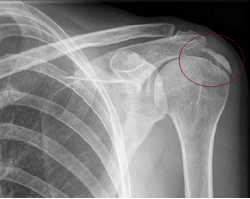

Calcificación en el hombro